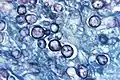

| Histoplasma capsulatum. Methenamine silver stain showing histopathologic changes in histoplasmosis | |